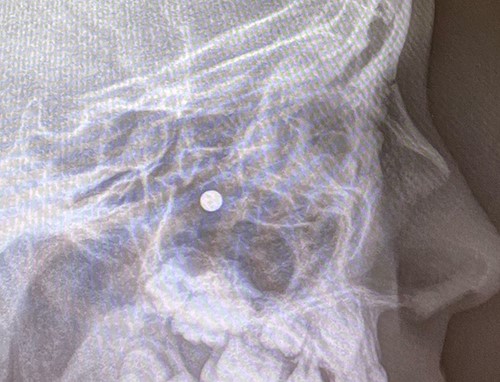

An 11 year-old male was transferred to the emergency room after being shot with a BB gun while playing. The patient’s custodian reports that he returned home with severe bleeding from bilateral nostrils which spontaneously resolved. The patient denies postnasal drip or salty taste. His medical history includes bipolar disorder and attention-deficit disorder managed with medications. On physical examination, an entry point wound is noticed in the skin of the left nasal sidewall (Figs 1 and 2). No active bleeding is noticed from anterior nasoscopy or in the posterior oropharynx exam. The rest of the head and neck examination is unremarkable. Plain X-rays performed in the emergency room confirm the presence of a metallic object in the right nasal cavity/paranasal sinuses (Figs 3 and 4). After consent is obtained, the patient is taken to the operating room and nasal endoscopy is performed. The left nasal cavity appears unremarkable. In the posterior nasal cavity, minimal bleeding and avulsed tissue is noticed after medialization of the middle turbinate. After minimal removal of tissue with pediatric Blakesley forceps, the BB bullet is visualized as lodged in the right posterior nasal cavity adjacent to the posterior attachment of the middle turbinate (Fig. 5). The bullet was then grasped with Takahashi forceps and removed after minimal endoscopic dissection (Fig. 6). Following extubation, the patient was observed for 8 h prior to discharge. During this period, no signs of recurrent epistaxis or cerebrospinal fluid rhinorrea were noticed.

In the past, non-powder guns were traditionally spring-loaded weapons that would release their projectile at a muzzle velocity (the speed of a projectile the moment it discharges from the muzzle of a gun) at less than 350 feet per second (fps). Recent advances in compressed-gas technology have increased muzzle velocities of non-powder guns to 900–1200 fps, which approximates the muzzle velocities of modern rifles with high-velocity cartridges [3]. Case series of penetrating injuries in the head and neck caused by BB and pellet guns have been previously reported [4, 5], but there are only two reports of similar injuries with BB guns in the paranasal sinuses [6, 7]. The path of the bullet is pertinent to the unusual presentation in our case: the entry point of the bullet was observed in the skin of left nasal sidewall at the level of left upper cartilage, and plain X-ray film showed the metallic bullet was located in the right nasal cavity. In the initial evaluation under the emergency situation, this raised concerns for a laterality error and mirroring of the plain X-ray image. This was readily addressed after discussion with the radiology technicians to confirm the imaging protocol was correct. After a thorough discussion of the procedure, the patient’s custodian consented to bilateral nasal endoscopy and need for possible bilateral intervention prior to proceeding to the operating room.